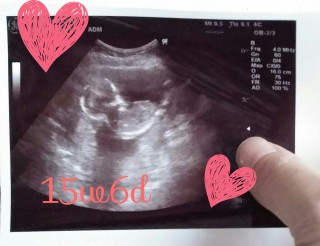

写真:15w6d:みぃさん

• おなまえみぃ

• ねんれい21

• 妊娠週15w6d

この日も元気に手足を動かしてました(^o^)ノ あまりに動きすぎてなかなかサイズ測れず先生もギブアップ( ゜д゜) 4週間前よりすごく成長しててこれからますます楽しみで、愛おしいです。